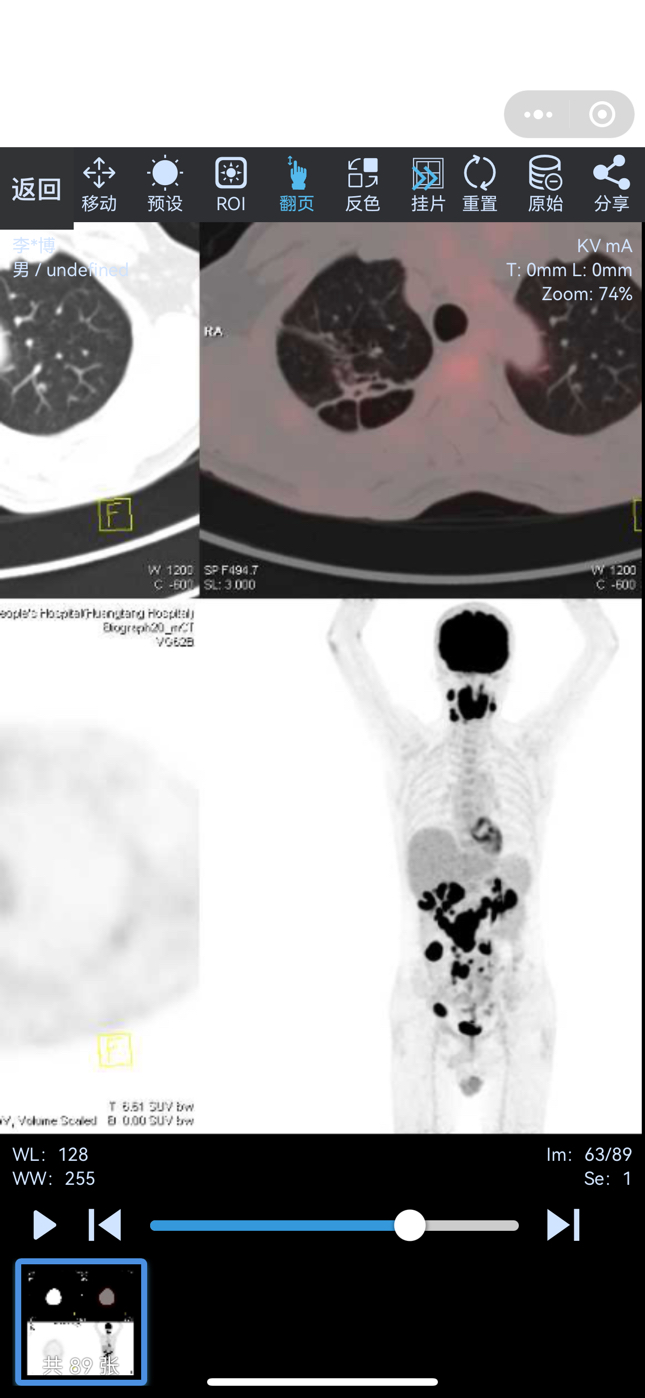

爸爸是EVB阳性弥漫大b淋巴瘤

病灶主要在小肠和大肠

今天做了PETCT

这是已经扩散到全身的意思了吗?

不是的,我只截了诊断意见,SUV有25,我重新放一下